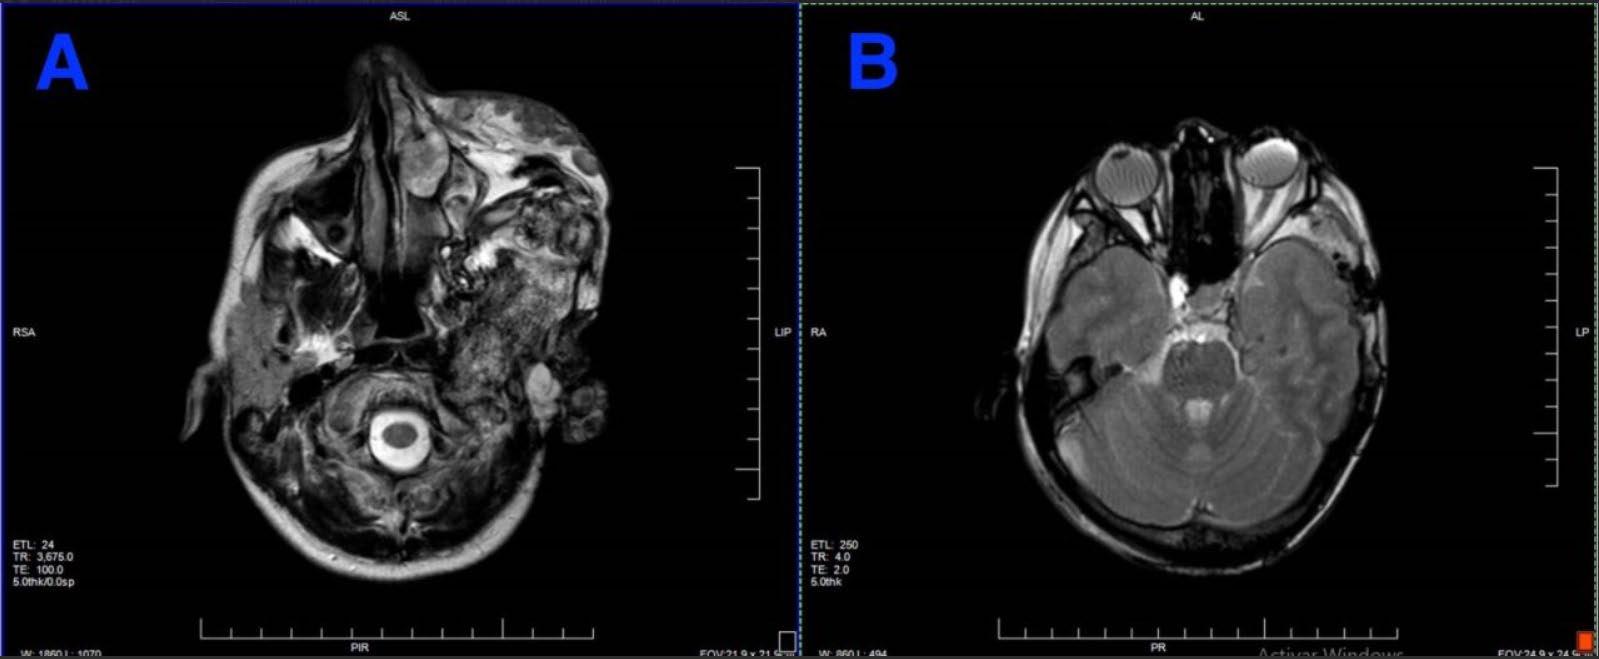

Helena Spicer

133 Favourable Response of Unresectable Giant Pinealoblastoma After Induction Chemotherapy and Craniospinal Radiotherapy: A Case Report

Laraichi R et al.

This issue includes six diverse, peerreviewed articles spanning rare case reports and forward-looking reviews. They include a rare presentation of immune checkpoint inhibitor-associated hydropneumothorax; a recurrent, aggressive, solitary plexiform neurofibroma with KRAS and AKT1 alterations; and a compelling case of unresectable giant pinealoblastoma responding favourably to induction chemotherapy followed by craniospinal radiotherapy. We also highlight a review of CAR-T cell-based immunotherapeutic strategies in hepatocellular carcinoma, a clinically significant case of aggressive angiomyxoma in term pregnancy, and a multi-omics exploration in non-small cell lung cancer aimed at advancing biomarker and pathway discovery.